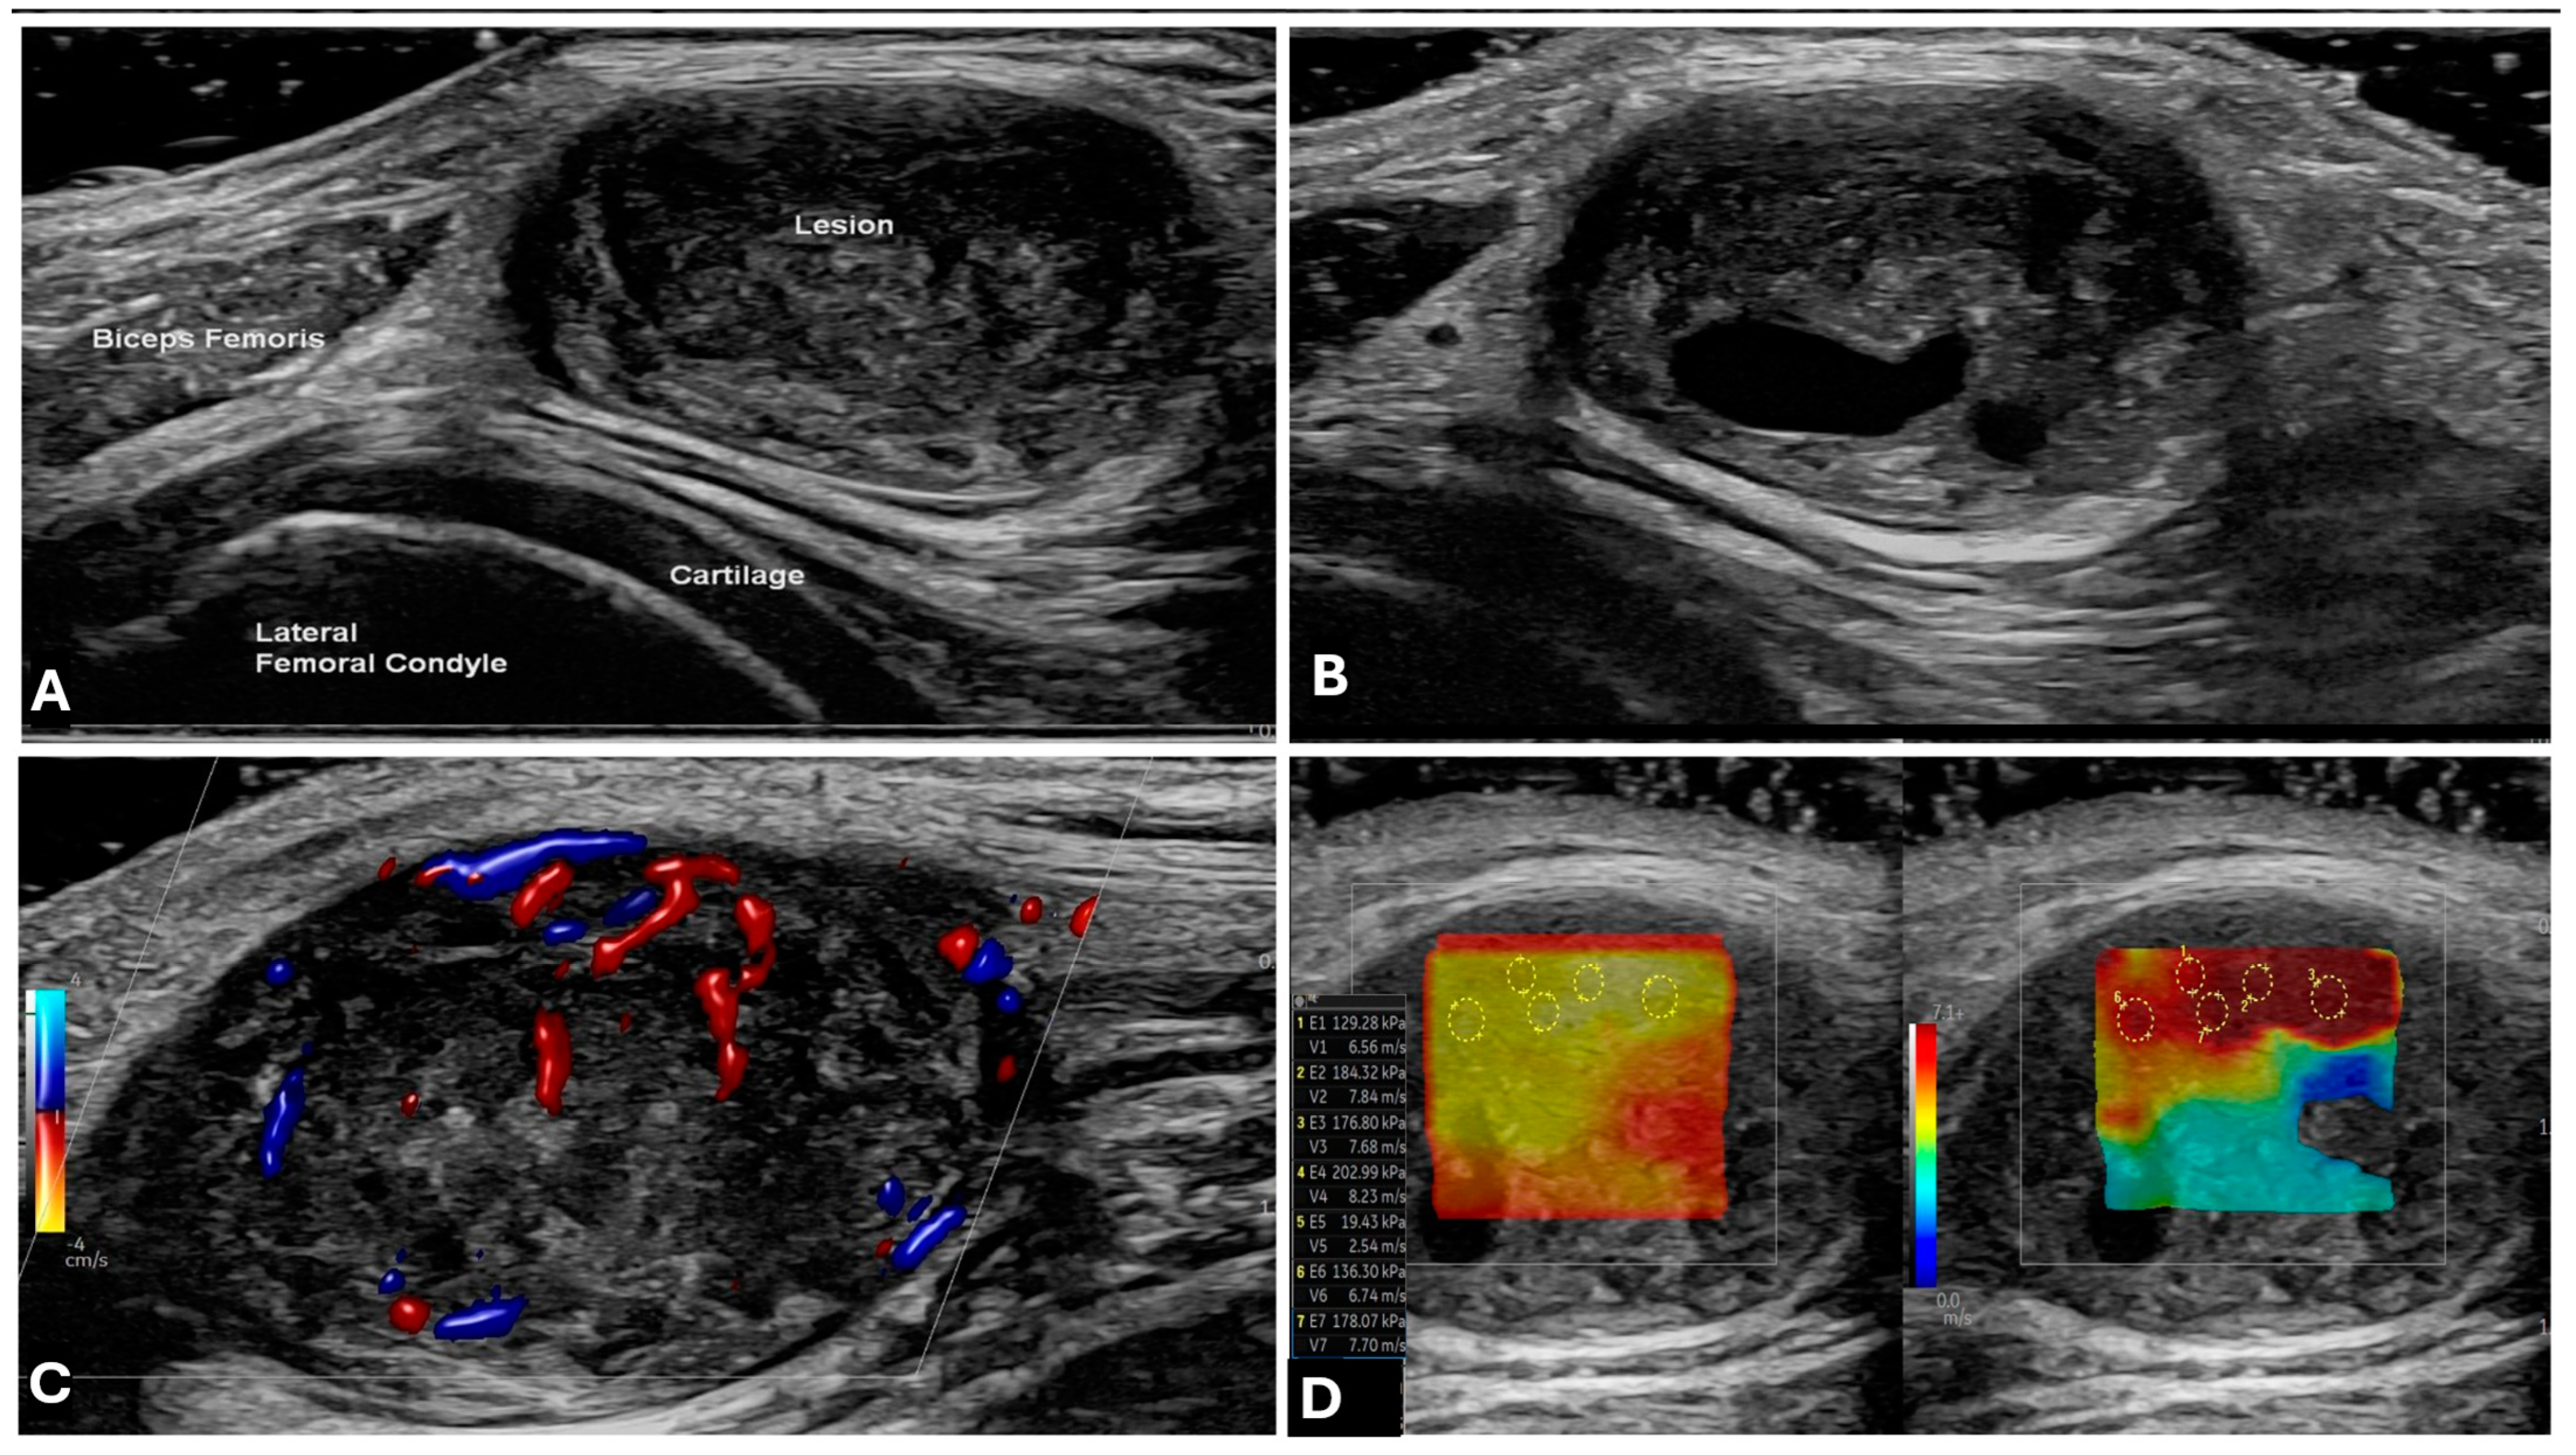

2.1. Ultrasound (US)

- Cantisani, V.; Orsogna, N.; Porfiri, A.; Fioravanti, C.; D’Ambrosio, F. Elastographic and contrast-enhanced ultrasound features of a benign schwannoma of the common fibular nerve. J. Ultrasound 2013, 16, 135–138. [Google Scholar] [CrossRef]

- Gowda, K.H.; Mishra, G.V.; Phatak, S.V.; Pavanan, A.; Dhande, R.P. Role of ultrasonography and strain elastography findings in peripheral nerve sheath tumor: A narrative review. J. Datta Meghe Inst. Med. Sci. Univ. 2022, 17, 187–195. [Google Scholar] [CrossRef]